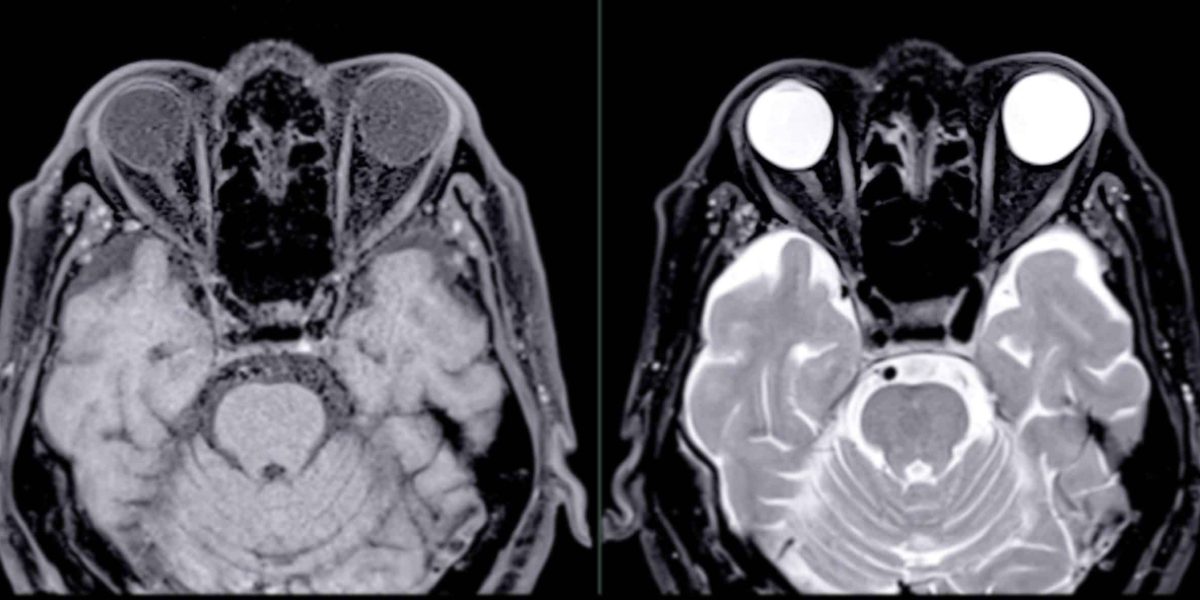

大腦灰白質

✔ 灰質+白質一起退化 → 形成失智症

灰質負責內容、白質負責傳遞。當兩者同時退化,就會出現典型認知功能障礙的記憶、語言、情緒與生活功能下降。

✔ 灰質: 負責記憶、判斷與情緒的大腦核心

灰質是大腦處理資訊的「主控台」。

✔ 白質:負責大腦訊號傳遞的訊號高速公路

白質就像大腦裡的「訊號高速公路」,讓不同腦區能快速交換訊息。